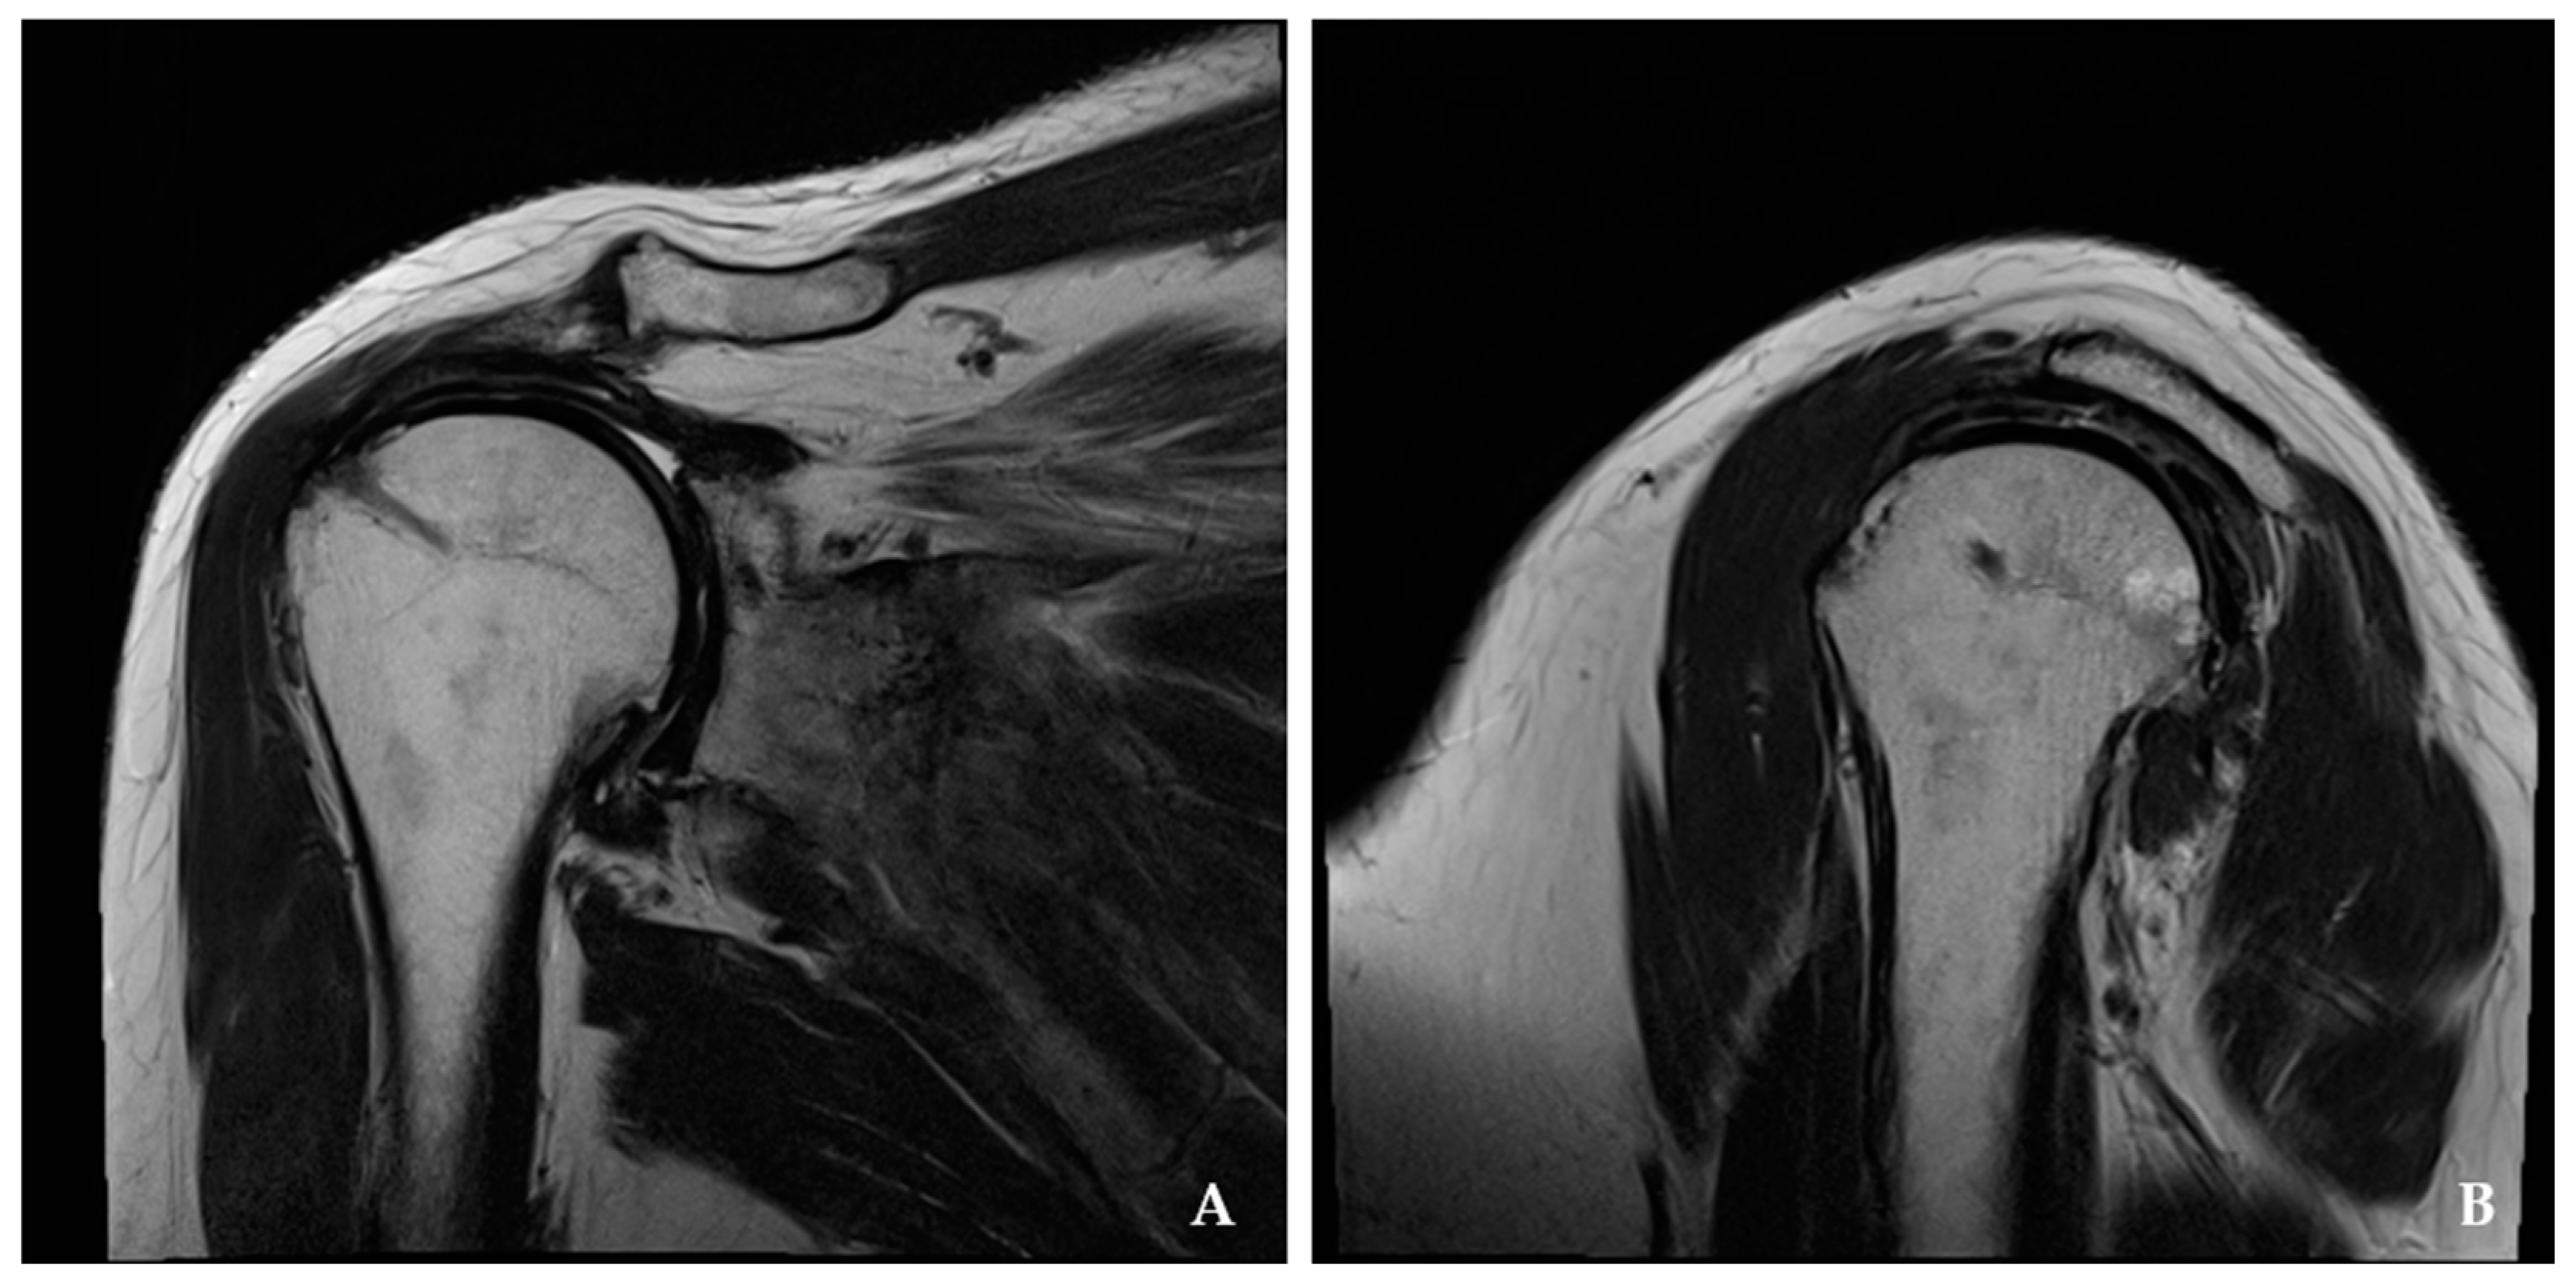

2.2. Clinical and Radiologic Assessment

3.3. Radiologic Assessment